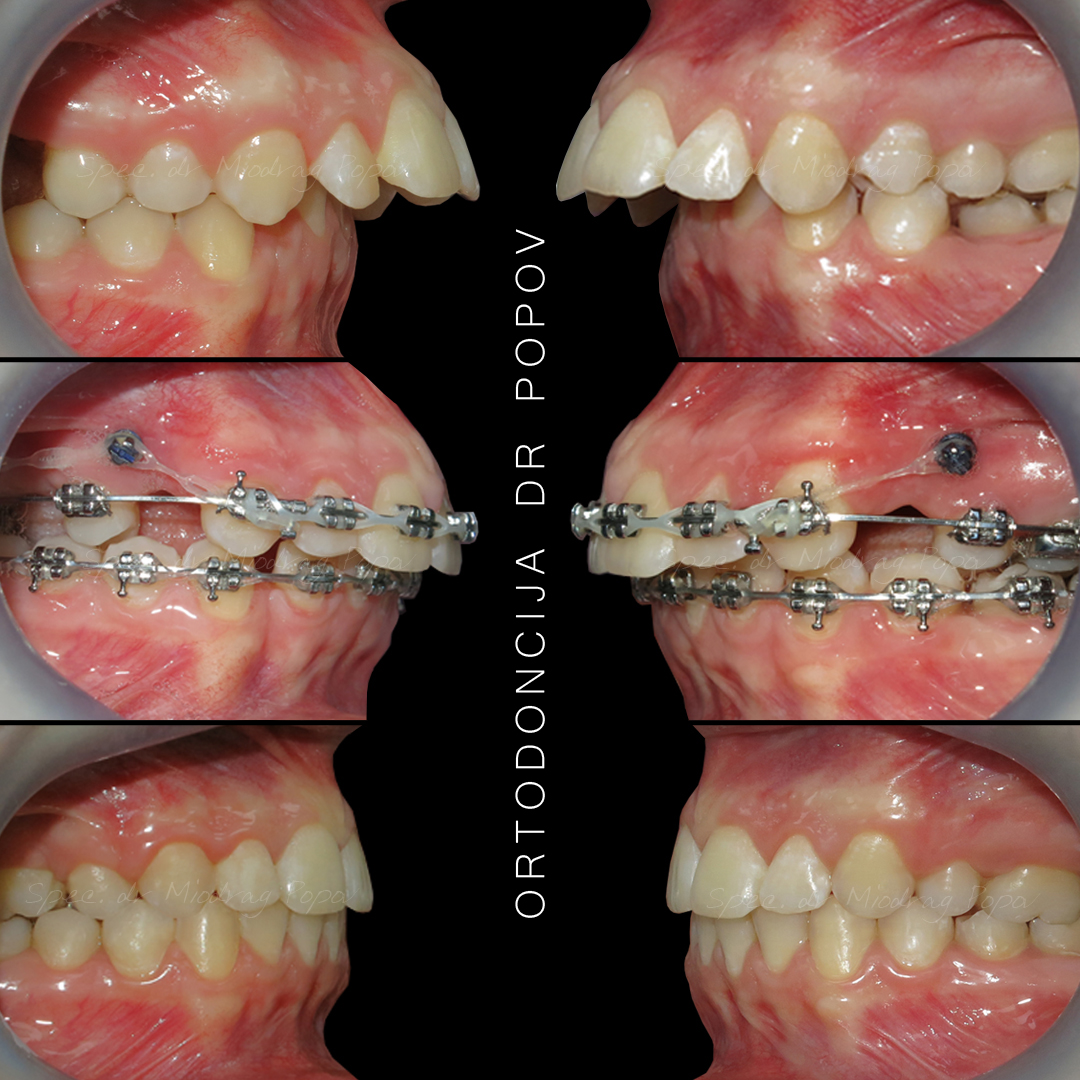

Slučaj ortodontske terapije II klase s vađenjem gornjih prvih predkutnjaka.

Na početku terapije, pacijentkinja je već imala izvađen gornji prvi kutnjak.

Tokom tretmana, svi prostori su zatvoreni, a profil lica transformisan.